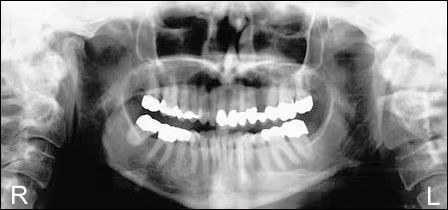

Panoramic Radiograph

Initial review of the panoramic radiograph was thought to reveal bifid mandibular condyles, a variant of normal. The maxillary sinuses were clear and their borders intact. There was a suggestion of recurrent caries in teeth #2 and #15.

Subsequent review of the panoramic film by an oral and maxillofacial radiologist indicated that there was also significant loss of bone density in the right ascending ramus and a loss of cortical integrity in the right condylar neck. Superimposition of air in the oropharynx over the right and left ascending rami made detection of this radiolucent area in the original film difficult.